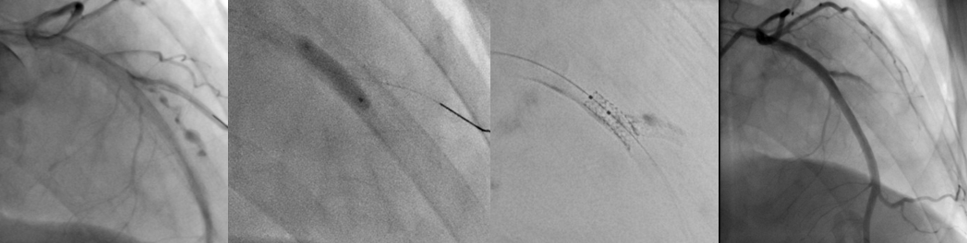

After diagnostic coronary angiogram, we proceeded to functional study of the D2 branch using 7Fr EBU 3.75 which confirmed functional significance with a RFR value of 0.75 and we proceeded with PCI. Ostium to proximal D2was pre-dilated with non-compliant 2.0 & 2.5 as well as cutting 3.0 balloon with recoil noted on angiogram after balloon inflation.IVUS imaging revealed underlying heavily calcified lesion and a sized-down 3.0 Shockwave balloon was deployed hoping to crack the calcium.Unfortunately the situation was complicated by perforation at very proximal D2 after Shockwave balloon inflation. The leak was localized at D2, yet balloon tamponade failed to seal the leak and hence 3.0 cover stent was deployed at D2 which seemingly sealed the leak.With a hope to reshape/align the carina, sequential dilatation of ostium D2 followed by kissing balloon inflation (KBI) with NC 3.5 in LAD & NC 3.0 in D2 was done. Unfortunately bleeding re-emerged after KBI, possibly due to crumpling of the proximal part of cover stent with possible extension of perforation into LAD. Thereafter the procedure became difficult as multiple balloon tamponade attempts in LAD/D2 failed to seal the leak. We ran out of options and had to deploy two cover stents in p-mLAD in order to control the leak. After stenting the LAD the leak improved but still some slow leak remained and we decided to go for reverse heparinization. Eventually the leak was much reduced to a minimal extent.

This case demonstrated how our team tackled an unfortunate PCI complication of diagonal branch perforation.

On hindsight, protruding less of the diagonal cover stent or stopping the procedure right after deploying diagonal cover stent may lead to a better outcome, hence the title "When Less Is More".